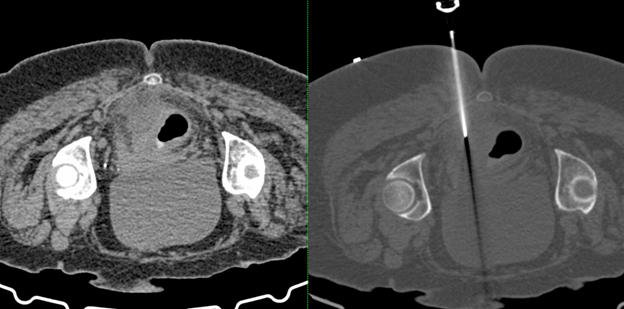

Perirectal Abscess Aspiration - Narayana Imaging & Diagnostics